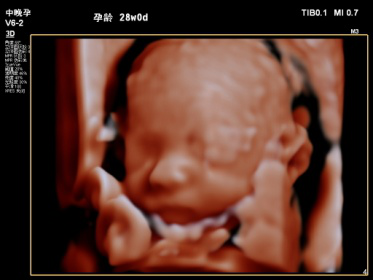

2019年县中医院功能科特引进飞利浦EPIQ5全身高档彩色多普勒超声,配备有心脏、腹部、浅表、腔内及三维容积等5把探头。其专有的purewave纯净波单晶技术,可提高在难以成像的患者身体中的穿透力,使成像更快捷、更清晰;飞利浦EPIQ5在孕期检查中也独具优势,通过图像的切割、旋转及高平面图像的分析,能直观、立体显示胎儿在母体子宫内的立体形态、表面特征、空间位置关系,尤其胎儿面部的三维成像,清晰、直观,准爸爸、准妈妈可以通过屏幕亲眼目睹胎儿的眼睛、嘴巴、鼻子和脸颊,甚至可以看到宝宝在妈妈肚子里运动、呼吸、吞咽、打哈欠、伸舌头等生理活动,非常直观。

每个孕妈妈都希望生个健康的宝宝,因此一定不要忘记这项重要的超声检查哦,不然错过时间可没有办法弥补了。我科室现已正式开展三维彩超,看这些可爱的宝宝!